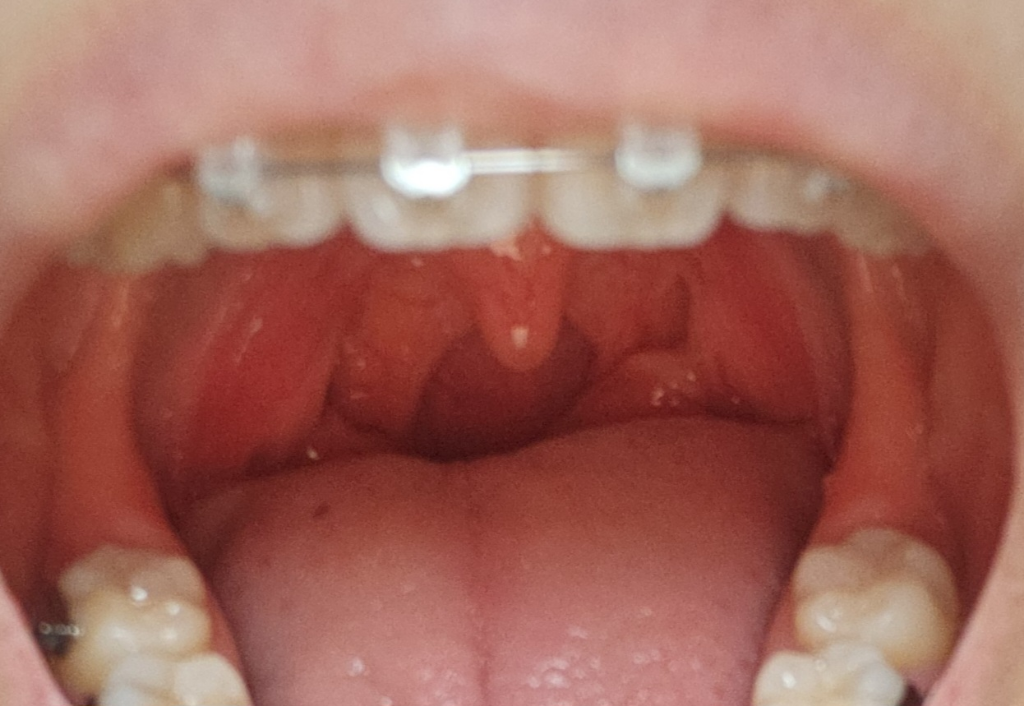

우선 제시하진 인후두의 사진은 양측 편도가 약간 과형성 되어있는 소견으로 보입니다.

말씁주신 증상은 이러한 증상은 식도염으로 인해 발생할 수 있습니다. 식도염은 식도 내부의 염증으로, 식도의 염증으로 인해 이런 증상이 나타날 수 있습니다. 이는 식도의 염증으로 인해 식도의 점막이 자극을 받고, 그로 인해 이물감이 느껴지며, 불편하게 느껴질 수 있습니다. 역류성 후두염이 원인이 아니라면 바이러스성 인후두염이 동반되었을 가능성도 고려해야 하겠습니다.